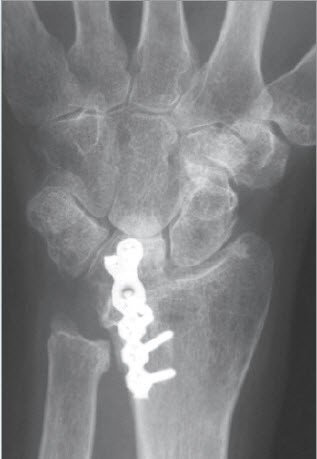

Bei einer isolierten Arthrose des unteren Speichen-Ellen-Gelenks (DRUG) findet sich vor allem eine schmerzhafte und eingeschränkte Vorderarm-Rotation. Die Beugung und Streckung im Handgelenk ist nicht oder nur minimal betroffen. In diesen Fällen wird eine isolierte Teilversteifung des Gelenkes nach Sauvé- Kapandji durchgeführt (Abb. 2). Bei diesem Eingriff wird das Ellenköpfchen mit der Speiche verbunden. Um die Vorderarm- Drehbewegung gleichwohl erhalten zu können, ist es erforderlich, ein Knochenstück der Elle herauszunehmen. Dieser Eingriff hat sich bewährt in Fällen, in denen das Gelenk isoliert zerstört worden ist. Eine solche Zerstörung kommt bei gewissen Formen der chronischen Polyarthritis vor, ferner auch als Folge von Speichenbrüchen.

Das Ellenköpfchen wird meistens mit einer Schraube zur Speiche fixiert. Diese Fixation ist nur bedingt übungsstabil, weshalb eine zusätzliche äussere Fixation in Form einer abnehmbaren Schiene erforderlich ist. Nach der Operation bleiben sowohl die Handgelenkbeweglichkeit als auch die Unterarm-Rotation in der Regel erhalten.